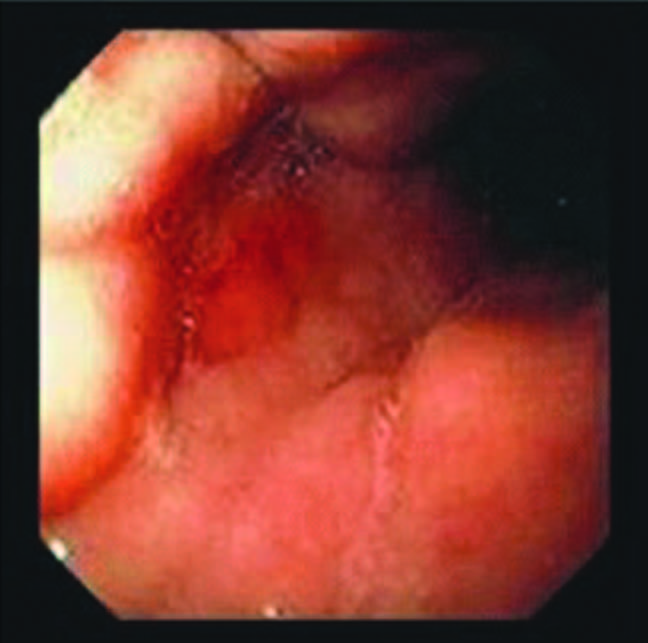

Coloscopie pour bilan d’anémie ferriprive. qu’est ce que c’est?

tumeur colique